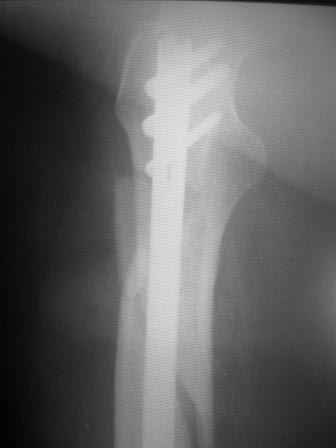

Уважаемый Максим, поддерживаю Вашу тактику на сто процентов. Более того скажу, что было в моей практике: установка блокированного бедренного стержня под местной анестезией (инфильтрационной), больная инвалид первой группы-анестезиологи отказались от больной. Выписана из отделения через 10-ть суток с объёмом движений до перелома (обслужи себя сам). Автору постера, чем меньше продержите до операции, тем лучше эфект от лечения (но без фанатизма).

Имя     : IMG_1580.JPG

Тип     : image/jpeg

Размер  : 29785 байтов

Url     : http://weborto.net:8080/pipermail/ortho/attachments/20101106/73ece197/attachment-0004.jpeg